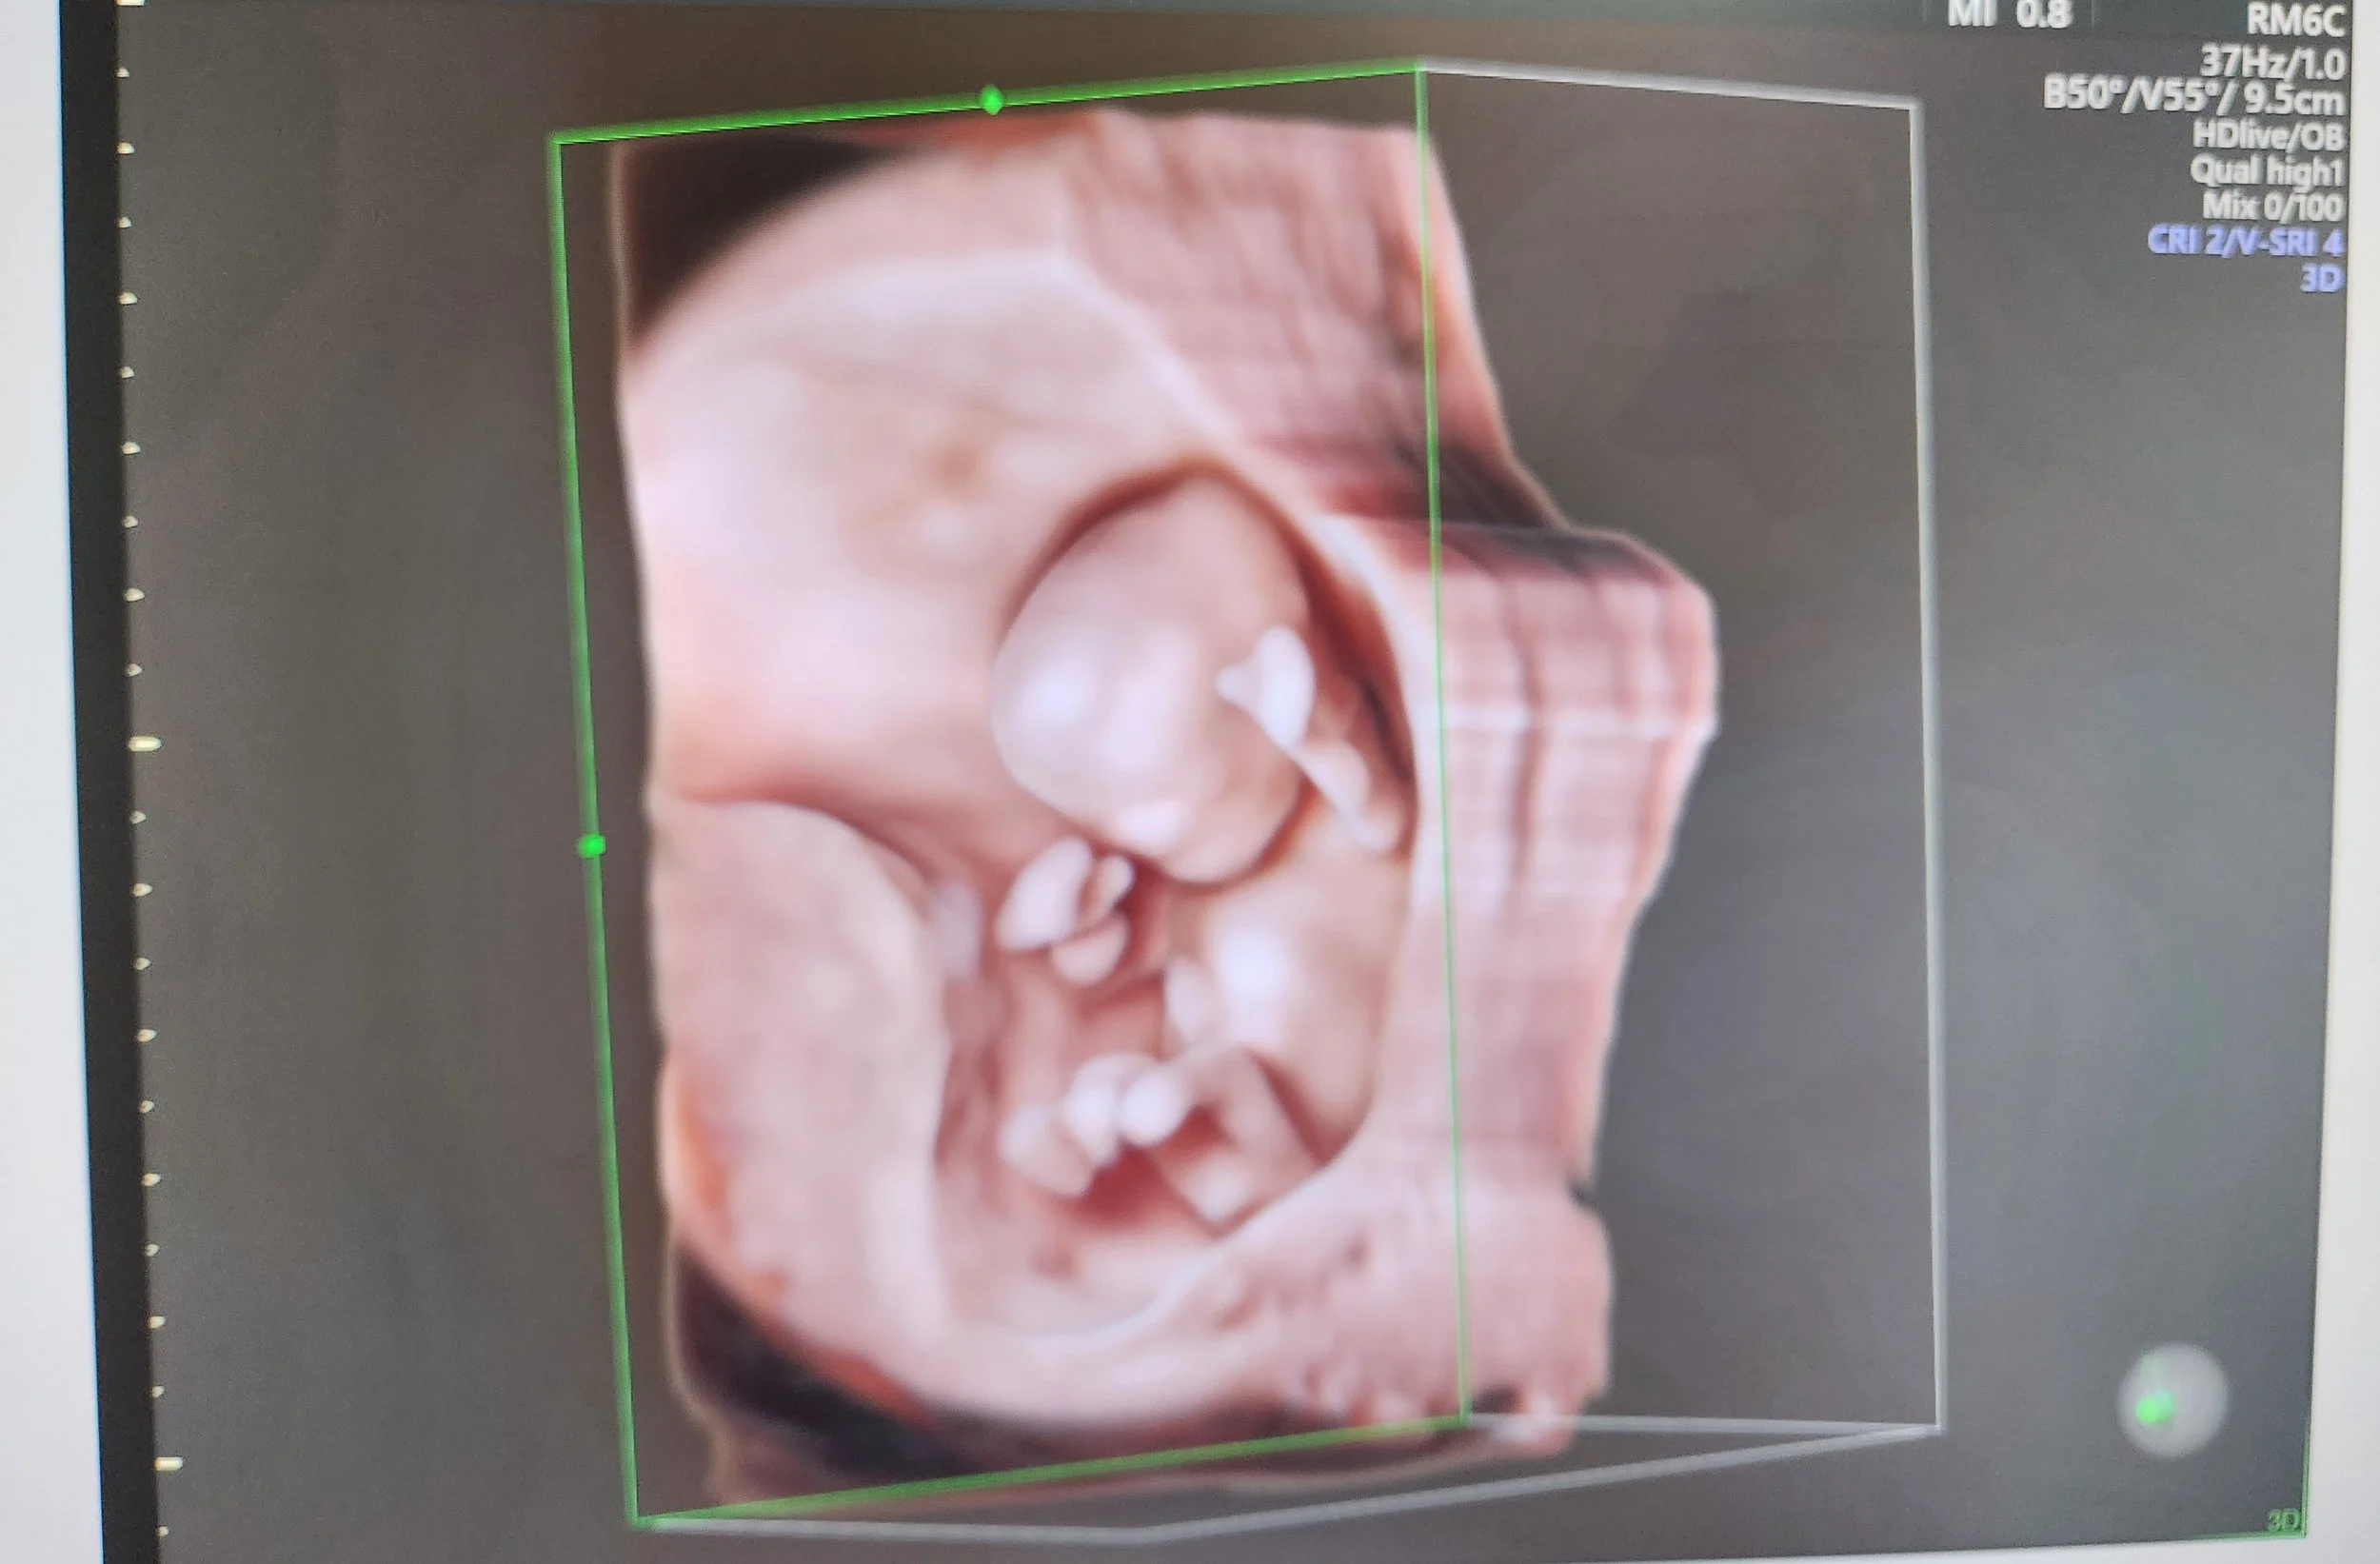

Cette échographie détaillée est réalisée entre 21 et 24 semaines d’aménorrhée. Le foetus pèse alors environ 400 à 600 grammes. C’est le moment idéal pour examiner en détail ses organes et vérifier leur bon développement. Le sexe foetal peut être révélé aux parents s’ils le souhaitent, et certaines malformations peuvent être dépistées.

Cet examen est réalisé entre 31 et 34 semaines d’aménorrhée et a pour objectif d’évaluer le bien-être et la croissance fœtale et de vérifier le bon développement des organes déjà étudiés au 2e trimestre.

Galerie d'échographies